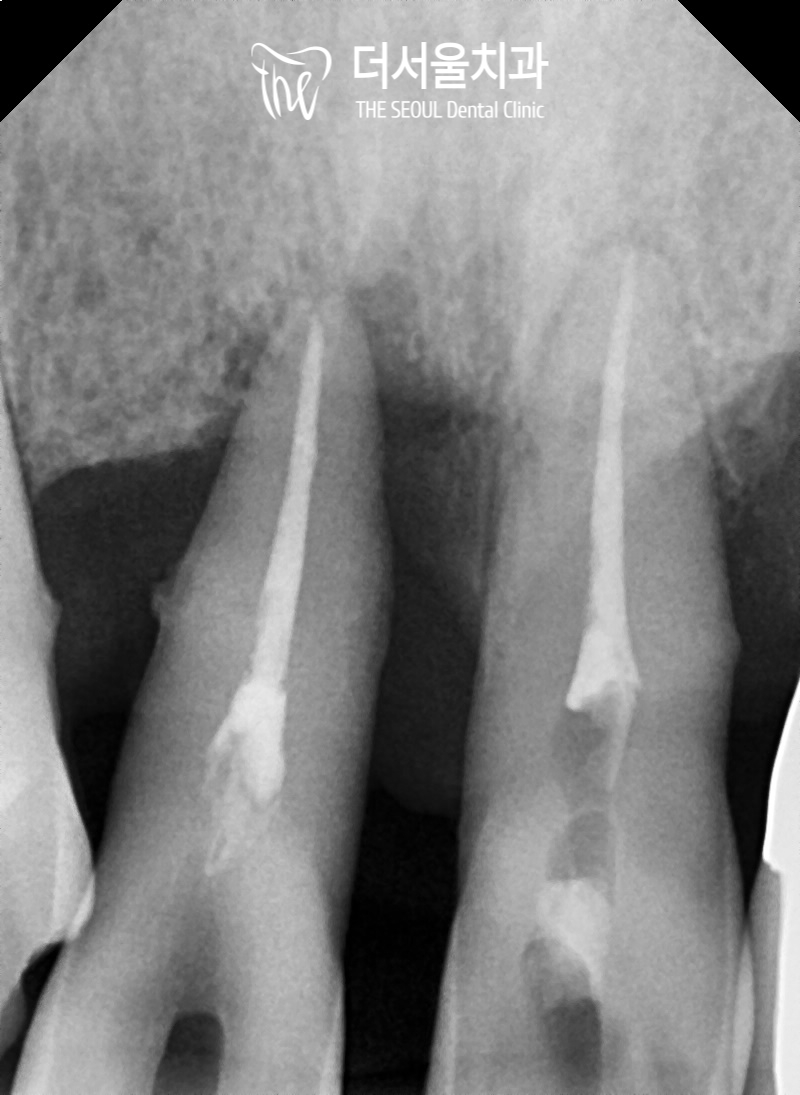

파노라마를 찍어 확인해 보니

이전에 신경치료를 받았던

흔적을 볼 수 있었는데요.

이곳에 문제가 생기게 되었고

제때 치료를 받지 않고 방치하게 되어

결국에는 전치부 치아 전체에서

흔들림과 통증, 구취, 치근 드러남 등

여러 복합적인 문제가 나타나게 된 것이죠.